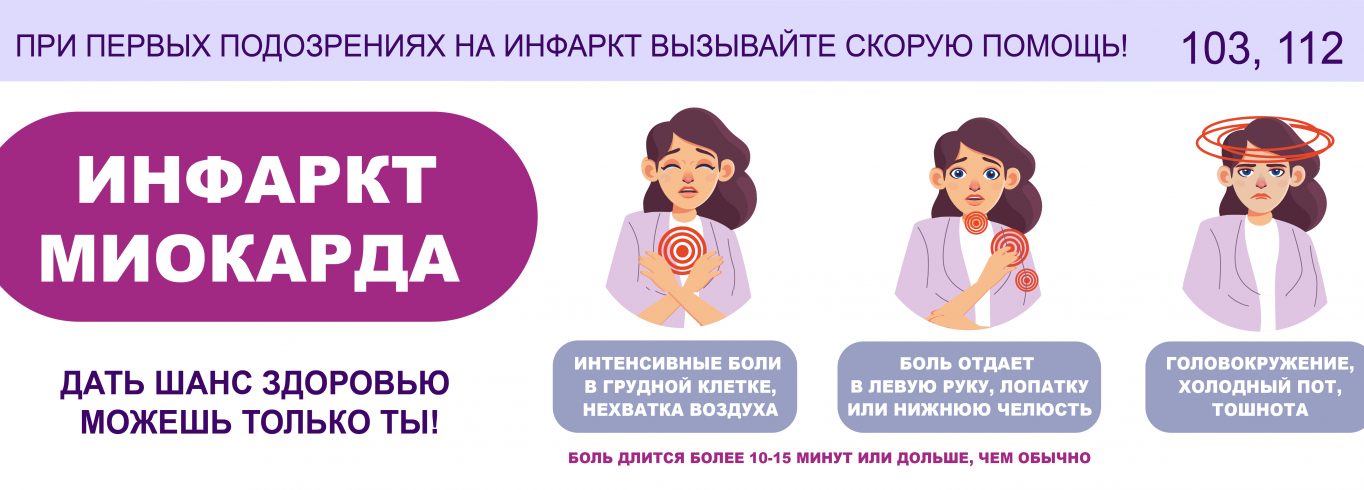

Этой теме было посвящено очередное заседание Комитета по устойчивому развитию Южно-Уральской торгово-промышленной палаты. Участники встречи, среди которых были представители Министерства здравоохранения Челябинской области, бизнеса, страховых компаний, обсудили возможности корпоративных стратегий в вопросах профилактики хронических неинфекционных заболеваний (ХНИЗ), таких как сердечно-сосудистые, онкологические, респираторные заболевания и диабет. Именно они являются главной причиной длительной нетрудоспособности персонала, скрытых экономических…